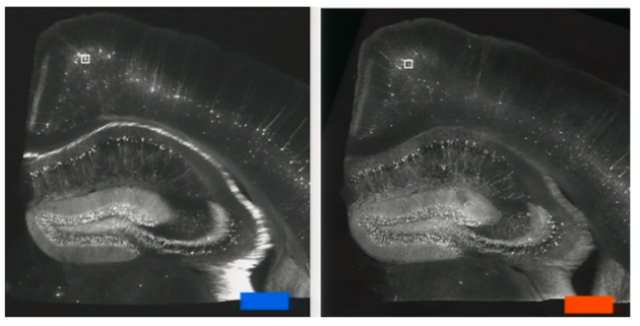

При контакте с водой клетка становится в 4,5 раза больше по сравнению с исходным размером во всех трёх измерениях. То есть, её общий объём увеличивается примерно в сотню раз.

Изменение размера образца позволяет исследователям получить более подробную информацию о клетке с помощью стандартных оптических микроскопов. Команда может продолжать использовать микроскоп, который обычно не в состоянии обнаружить детали размером менее 300 нанометров. Клетки при использовании данного метода заполняются обыкновенной водой, а потому становятся прозрачными, и учёные могут видеть то, что происходит внутри.